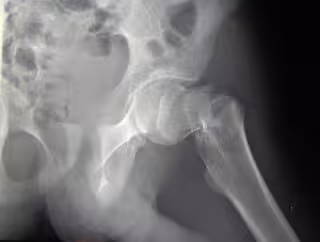

Un 60% de los mayores presenta nivel inadecuado de vitamina D

hueso

BOOYABAZOOKA/CREATIVE COMMONS